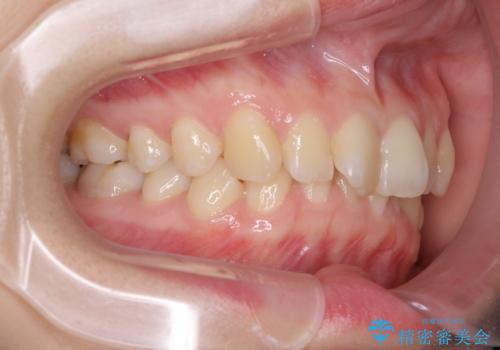

インビザラインによる前歯の矯正治療

- 口元の深い咬み合わせ(ディープバイト)を気にして来院された患者様です。

インビザラインによる上下歯列の遠心移動(後方移動)により、口元のデコボコとディープバイトを改善することとしました。

下顎左右の犬歯とその後ろにある第一小臼歯、計4歯がシミュレーション通りに動かずディープバイトがなかなか改善されませんでした。

マウスピースの再製作を何度か行いましたがうまくいかないため、部分的にワイヤー矯正を併用することを提案しました。しかし、最も気になっていた前歯のデコボコはきれいに改善されたため、これ以上治療を希望されず、治療を終了することとしました。(今後気になった際には再開する予定です)